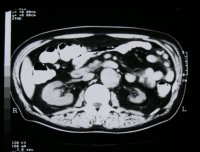

Neben der Anamnese, körperlicher Untersuchung, Messung des Blutdruckes sowie der Laboruntersuchungen: Urinstatus, Serumkreatinin und -Elektroylte ist die Sonographie zur Feststellung einer einseitig kleinen Niere zielführend (Abbildung 10a). Zur Diagnostik zählt fernerhin die NFZG (Abbildung 10b) bzw. Computertomographie.

Computertomographie zur Diagnostik der kleinen Niere. Zum Beispiel eine pyelonephritisch veränderte linke Niere im Computertomogramm und im weiteren Beispiel CT und Organpräparat einer rechtsseitigen kleinen Niere.

Und in einem weiteren Beispiel CT und Organpräparat einer rechtseitigen "kleinen Niere" (Abbildung 11, 12ab).